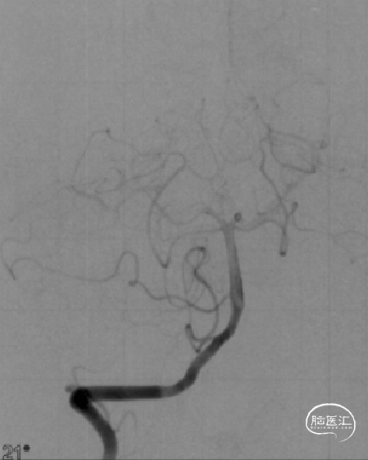

➤术前DSA检查

右侧大脑中动脉重度狭窄,左侧前循环未见明显异常。

病变部位: 右侧大脑中动脉M1段重度狭窄;狭窄率: 75.6%;狭窄长度: 6.10mm;参考远端血管直径: 1.27mm。

2022-07-27 术前正位

2022-07-27 术前侧位